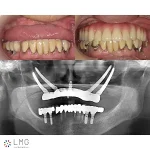

上顎左上シングルザイゴマ、5本インプラント埋入

手術後パノラマX線写真

セデーション(静脈内鎮静法の麻酔)により、骨のなかった左上ザイゴマと5本インプラント埋入